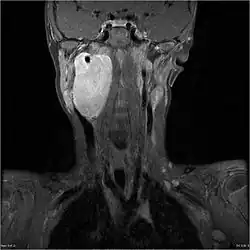

MRI of a ganglioneuroblastoma found in the head and neck of a 7 year old Caucasian male.